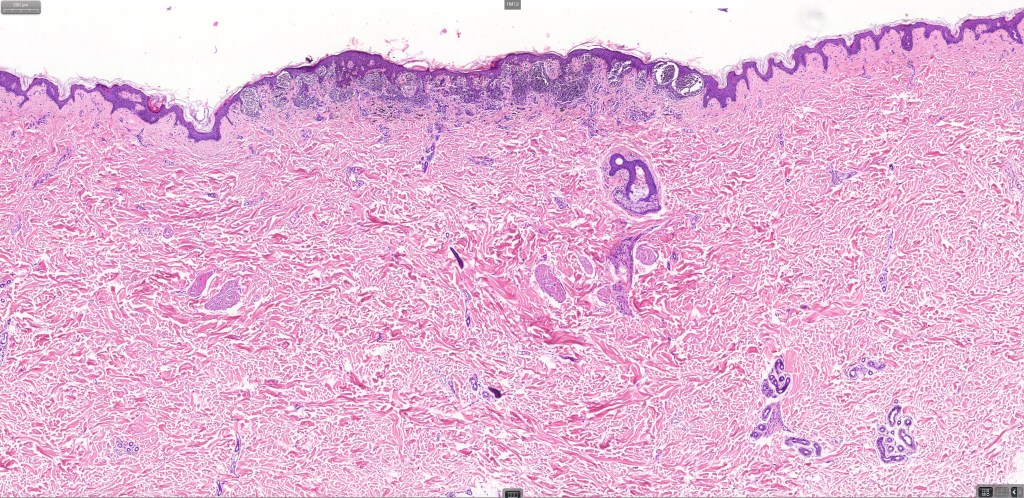

•Variant of Spitz nevus, readily identifiable at scanning magnification in the majority of cases

•Symmetrical and circumscribed with a characteristically flat lower border

•Vertically orientated oval junctional nests

•Maturation in compound variants

•80 % kinase fusions (NTRK3-58%), HMB45 diminishes with depth in compound lesions